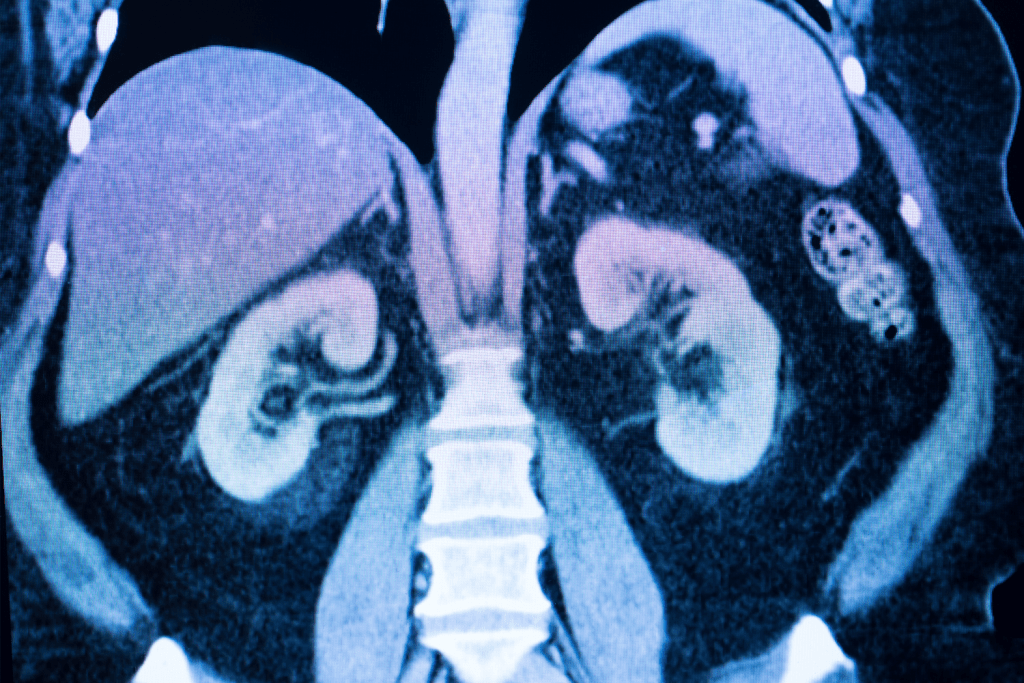

Detection Capabilities for Tumors, Cysts, and Vascular Anomalies

Kidney MRI scans are great at finding different kinds of problems, like tumors, cysts, and blood vessel issues. The high sensitivity of MRI makes it a top choice for finding kidney diseases. Early detection means doctors can act fast.

MRI vs. CT Scans for Kidney Assessment

MRI and CT scans are both used to check the kidneys. But they are different. MRI shows soft tissues better than CT scans. This makes MRI great for looking at complex kidney structures and finding problems like tumors or cysts.